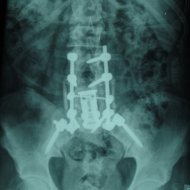

Tedavi:

Tümörlere yaklaşım olarak doku tanısı çok önemlidir. O nedenle eğer tümörün odağı bilinmiyorsa ya da omurganın kendi tümörüyse öncelikle biyopsi almak gerekir. Ardından tümörün cinsine göre kemoterapi, radyoterapi, ameliyat ya da bunların kombinasyonu uygulanır.